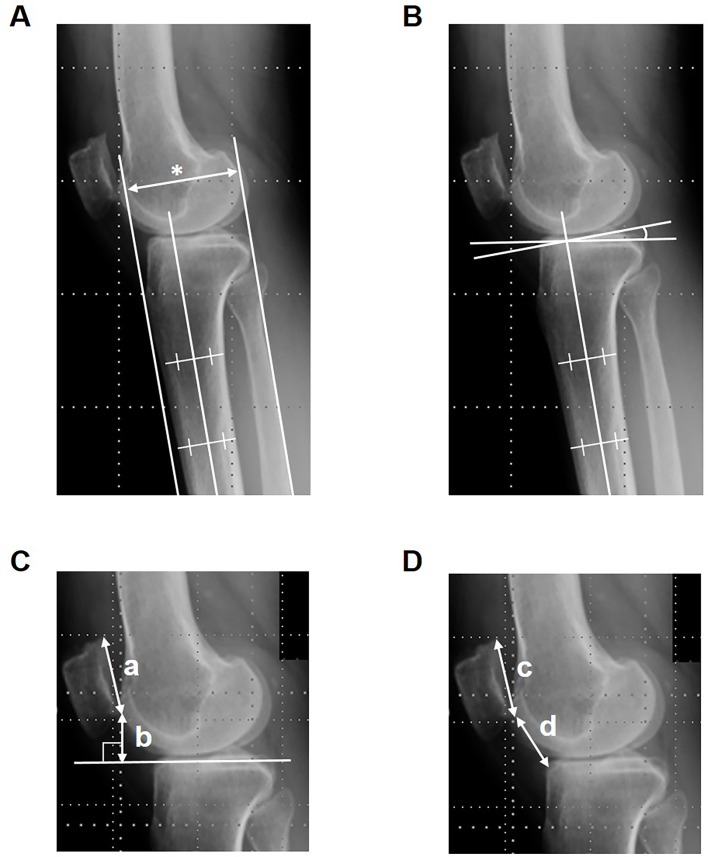

Methods: One hundred consecutive knees with osteoarthritis that underwent OWHTO (50 knees) or CWHTO (50 knees) were investigated retrospectively. The femorotibial angle (FTA) was measured on AP radiographs of the knee. AP displacement of the TT, posterior tibial slope (PTS), the modified Blackburne-Peel index (mBPI), and the modified Caton-Deschamps index (mCDI) were measured on lateral radiographs of the knee.